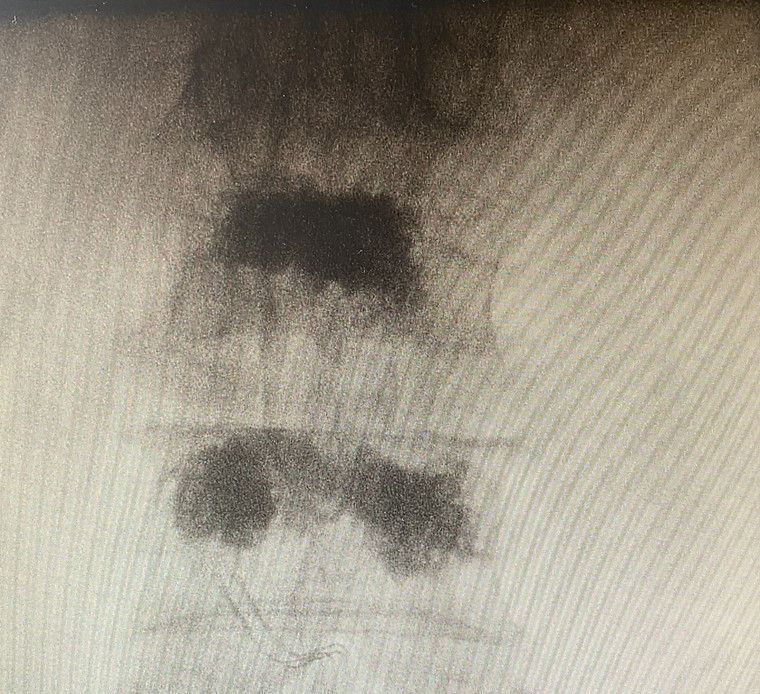

Rekonstruktive Wirbelsäulenchirurgie

Wirbelsäulenpathologien werden durch minimalinvasive rekonstruktive Eingriffe versorgt.